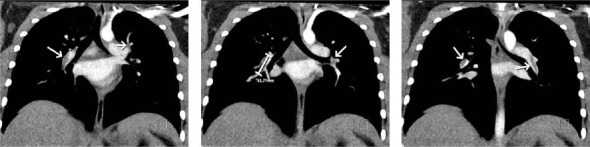

Pulmonary embolism is a rare, but serious, potential perioperative complication and crisis. We present a case of a 12-year-old female undergoing distal femoral and proximal tibial osteotomies with internal fixations who experienced acute onset hypercapnia, tachycardia, and prolonged minimal responsiveness following deflation of the tourniquet and cessation of inhaled sevoflurane. CT-chest demonstrated bilateral partially occlusive filling defects of the pulmonary vasculature. We concluded that the patient experienced a pulmonary embolism resulting in V/Q mismatch, retained sevoflurane, and ultimately delayed emergence.

Abstract Image